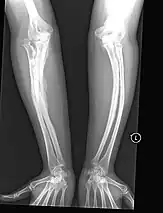

The main symptom of osteogenesis imperfecta is fragile, low mineral density bones; all types of OI have some bone involvement.[5] In moderate and especially severe OI, the long bones may be bowed, sometimes extremely so.[28] The weakness of the bones causes them to fracture easily; a study in Pakistan found an average of 5.8 fractures per year in untreated children.[29] Fractures typically occur much less after puberty, but begin to increase again in women after menopause and in men between the ages of 60 and 80.[1]: 486

- Type V – Having the same clinical features as type IV, it can be clinically distinguished by observing a "mesh-like" appearance to a bone biopsy under a microscope. Type V can be further distinguished from other types of OI by the "V triad": an opaque band (visible on X-ray) adjacent to the growth plates; hypertrophic calluses (abnormally large masses of bony repair tissue) which form at fracture sites during the healing process; and calcification of the interosseous membrane of the forearm,[50] which may make it difficult to turn the wrist.[1]: 429 Other features of this condition may include pulled elbow, and, as in other types of OI, long bone bowing and hearing loss.[64] Cases of this type are caused by mutations in the IFITM5 gene on chromosome 11p15.5.[64][49] The separation of type V from type IV OI, its clinical type, was initially suggested even before its genetic cause was known, by Glorieux et al. in 2000.[50][65] Type V is relatively common compared to other genetically defined types of OI—4% of OI patients at the genetics department of the Brazilian Hospital de Clínicas de Porto Alegre were found to have it.[66]

Diagnosis is typically based on medical imaging, including plain X-rays, and symptoms. In severe OI, signs on medical imaging include abnormalities in all extremities and in the spine.[97] As X-rays are often insensitive to the comparatively smaller bone density loss associated with type I OI, DEXA scans may be needed.[5]: 1514